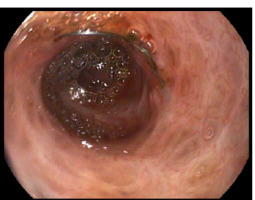

Figure 1

Cholangioscopic view of an uncovered, self-expanding metal stent obstructed by scar tissue. Nitinol weave of the overgrown stent can be seen. During previous procedures multiple biopsies and cytologic brush sweeps ruled out the presence of neoplastic lesions